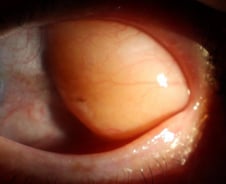

눈의 망막에서 나타나는 변화를 통해 파킨슨병을 조기에 발견할 수 있는 단서가 한국에서 밝혀졌다. 연세대 용인세브란스병원 안과 지용우 교수, 문채은 박사 후 연구원, 이승재 전임의 연구팀은 동물 모델을 이용한 연구에서 망막의 기능적·구조적 변화가 파킨슨병의 뇌신경 퇴행 이전 단계부터 나타날 수 있음을 확인했다고 5일 밝혔다. 파킨슨병은 뇌에서 알파-시누클레인 단백질이 비정상적으로 쌓이면서 신경세포 기능이 점차 저하되는 대표적인 퇴행성 뇌질환이다. 건강보험심사평가원 자료에 따르면 국내 파킨슨병 환자 수는 2024년 기준 약 14만3441명으로, 2020년(12만5927명) 대비 14% 증가했다. 눈의 망막은 발생학적으로 뇌와 같은 중추신경계의 일부분이다. 또한 비교적 간단한 비침습적 검사로 구조와 기능을 반복적으로 관찰할 수 있어, 파킨슨병으로 인한 변화를 탐지하기에 적합한 장기다. 기존 연구에서 파킨슨병 환자의 망막에서 기능적인 저하와 구조적인 변화가 보고된 바 있으나, 이러한 변화가 질병의 어느 시점부터, 어떤 기전으로 시작되는지는 명확히 밝혀지지 않았다.